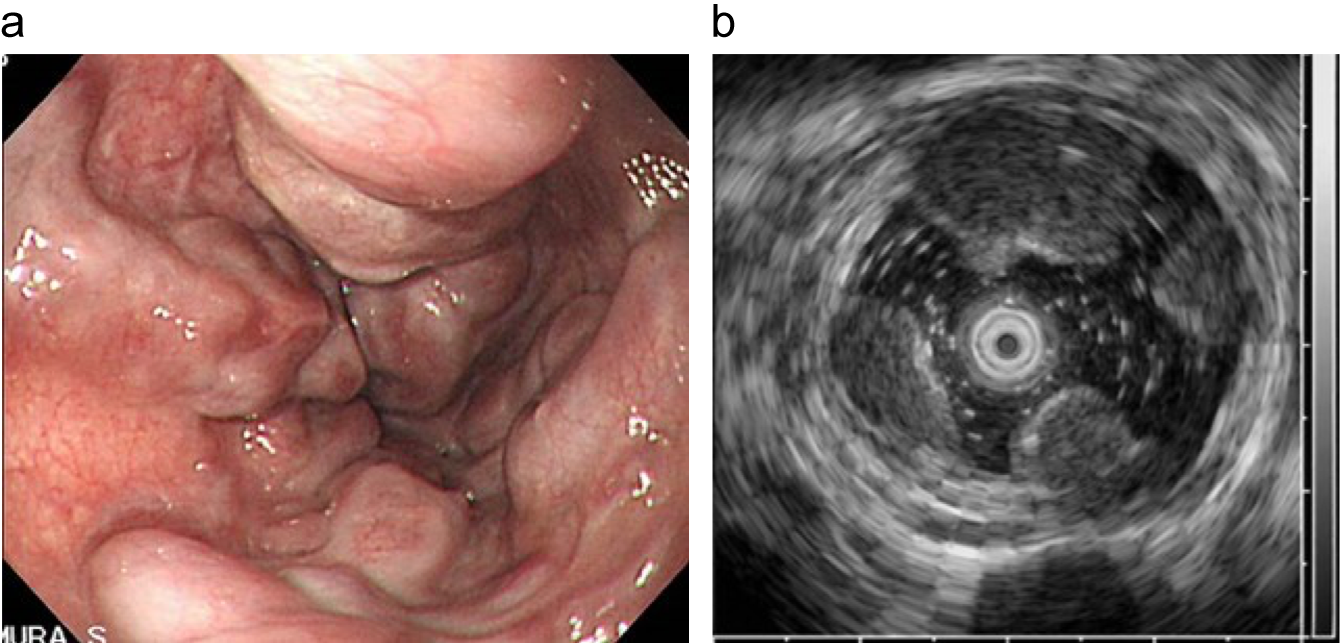

症例画像1:内視鏡、超音波内視鏡像

a: 内視鏡画像

b: 超音波内視鏡像

出典

img

1: 著者提供